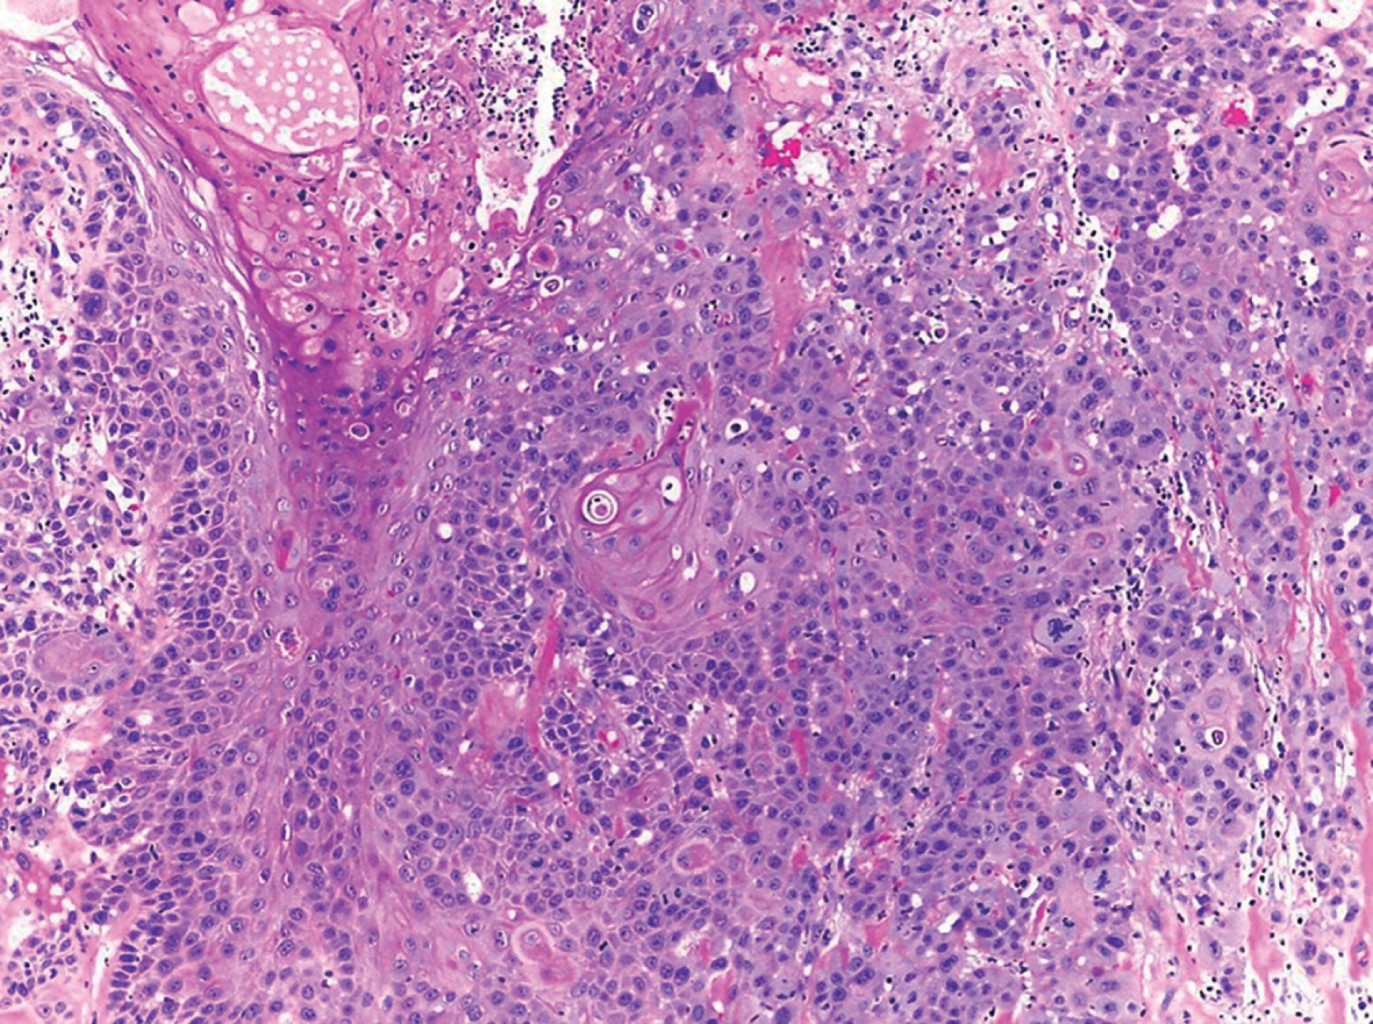

HISTOPATOLOGíA

Las imágenes histopatológicas muestran patrones de diferentes carcinomas cutáneos, principalmente de carcinoma epidermoide en 71%.3 El resto corresponde a carcinoma basocelular, melanoma, sarcoma, entre otros.1,3

Paciente del sexo masculino, de 43 años de edad, originario y residente de Guerrero, desempleado. Acude por una dermatosis localizada a tronco, del que afectaba tórax posterior en la región escapular izquierda; constituida por una neoformación exofítica, de 10 × 8 cm en su eje mayor, ulcerada, con costras melicéricas y secreción purulenta en su superficie, de bordes irregulares y bien definidos (Figura 1). Presentaba también una segunda neoformación en región escapular y hombro de lado izquierdo, de aspecto atrófico, de 9 cm de diámetro, con escama amarillenta y gruesa en su superficie, de bordes mal definidos (Figura 2), ambas de evolución crónica, dolorosas, que emitían olor fétido. Presentaba además adenopatías palpables ipsilaterales. Como antecedentes de importancia refirió haber sufrido una quemadura de tercer grado extensa en tórax y extremidades superiores con gasolina 22 años antes. El padecimiento actual lo inició hace tres años, con una "bola de rápido crecimiento" (sic paciente), la cual más tarde se ulceró en forma espontánea, acompañándose de sangrado y dolor progresivo. Acudió con especialista en Guerrero quien realizó biopsia y lo canalizó a este centro dermatológico con el diagnóstico de carcinoma epidermoide moderadamente diferenciado queratinizante, invasor (Figuras 3, 4 y 5). Al tratarse de un tumor de alto riesgo, el paciente fue referido a un hospital de tercer nivel en donde falleció al mes del internamiento debido a choque séptico y fascitis necrotizante.

Figura 4